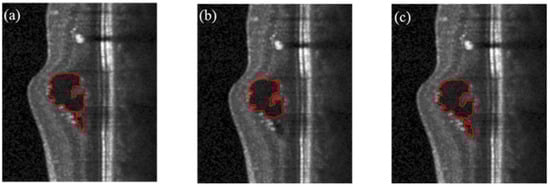

This paper proposes an automatic segmentation method with multiple operating directions. The selection of the number of directions has been verified by experiments and theoretical analysis. When designing the algorithm, based on experience, we believe that an arbitrarily shaped target with a closed contour needs to be segmented in eight directions, but in actual experiments, we found that segmentation in four directions is sufficient to determine any closed curve contour. In order to better explain this, we considered four directions, six directions, and eight directions, and calculated the evaluation index of the segmentation results in the corresponding number of directions. Figure 7 shows the segmentation results of the three cases. Table 2 shows four evaluation indicators.

It can be seen from Figure 7 that the four-direction operator and eight-direction operator have better segmentation performance than the six-direction operator, and the six-direction operator cannot fully identify the cyst. From the results of the evaluation indicators, the difference between the Dice index and the F1-score is very small, and they have similar segmentation performance. We choose the four-direction operator instead of the eight-direction operator, considering the following aspects:

Figure 7. Segmentation results of the operator in different directions, (a) the result of 4-direction operator; (b) the result of 6-direction operator; (c) the result of 8-direction operator.